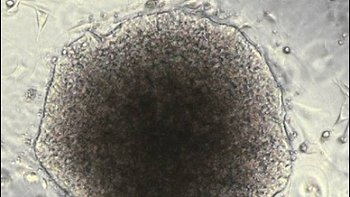

En la foto una célula madre, la que sería responsable de la metástasis del cáncer.

"Hemos descubierto que las células madre tumorales, a pesar de que constituyen el uno por ciento o el dos por ciento de la población de las células tumorales, son las más importantes desde el punto de vista de la agresividad, determinando la metástasis y la reaparición" del cáncer, comenta Ruggero De Maria, oncólogo del ISS.